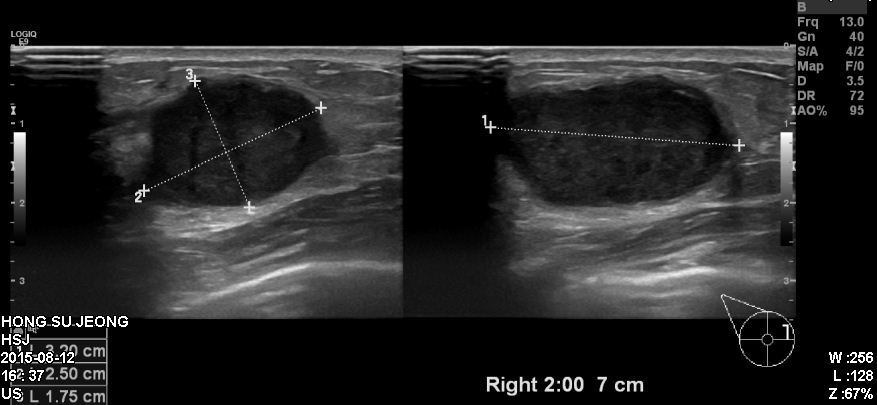

우측 유방에 만저지는 몽우리로 내원하신 30대 여성분으로 우측 유방 2시 방향에서 7cm

떨어진 곳에 의심 스러운 혹 조직검사 시행하여 우측 침윤성 유관암 진단 되었습니다.